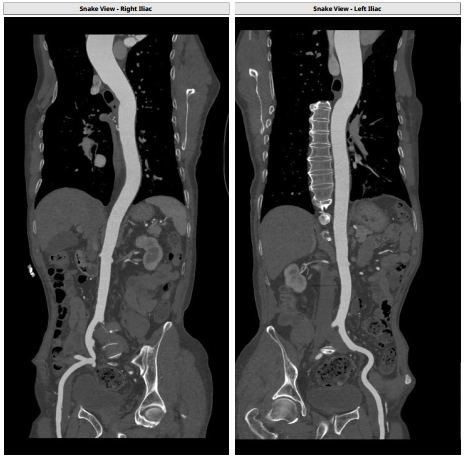

双侧股动脉血管走形稍迂曲,未见明显钙化,双侧均为低分叉;髂总动脉—降主动脉走形平直,未见明显钙化;主动脉弓部走行相对顺滑。

主/辅入路:穿刺右侧股动脉预置缝合器为主入路(Myval™ 14F血管鞘),左侧股动脉为辅入路;

外周入路血管条件,主动脉弓、降主动脉及腹主动脉部分部位存在钙化。